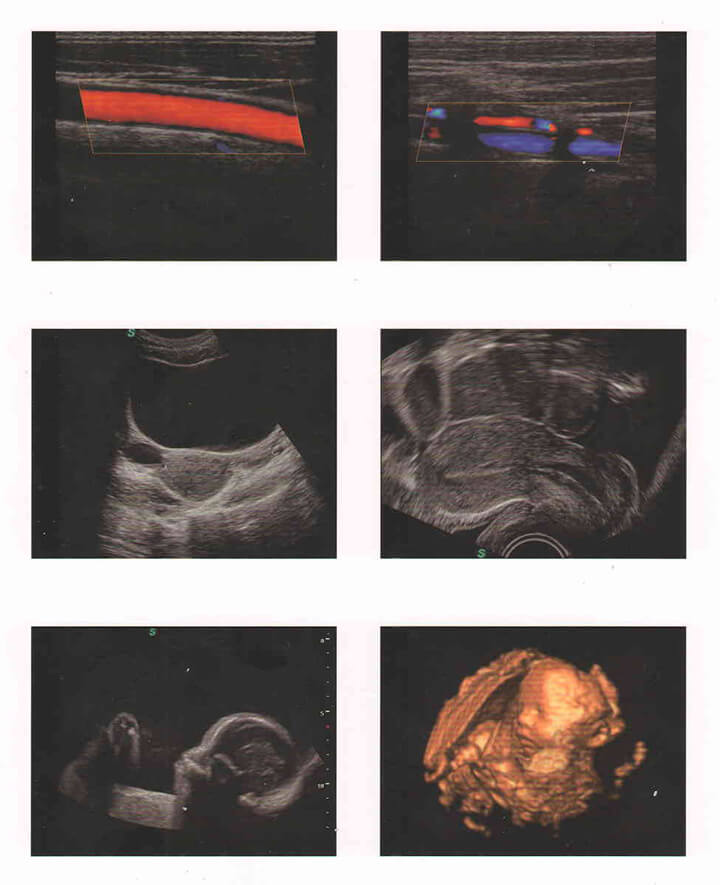

Sonoscape S11

Máy siêu âm Doppler màu 4D SonoScape S11 được thiết kế với màn hình LCD có độ phân giải cao 15 inch với cánh tay khớp nối nhanh và thiết kế xe đẩy nhanh, 4 cổng cắm đầu dò hoạt động sẵn, ứng dụng trong Duplex, Doppler màu, DPI, PW Doppler, hình ảnh hài hòa mô, sp-scan đốm lốm đốm, hình ảnh toàn diện

Tổng quan về máy siêu âm màu 4D Sonosacape S11

Sonoscape S11 được biết đến là máy siêu âm 4D bàn đẩy có chi phí tối ưu nhất hiện nay

• Màn hình LCD độ nét cao 15 inch với cánh tay khớp nối

• Thiết kế xe đẩy nhỏ gọn và nhanh nhẹn